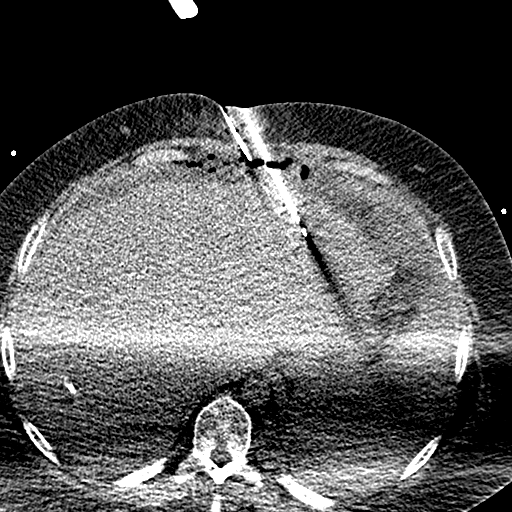

79 M with PMH of CKD, HLD, prostate cancer s/p prostatectomy + radiation presenting with feelings of fogginess, upset stomach, and diarrhea. Originally worked up at OSH, imaging concerning for a hepatic mass.

148/77 mmHg / 95 bpm / 15 breaths/min / 98.1°F / 98 ORA

sclera anicteric, no jaundice

AST 112, ALT 34, Alk Phos 202, CEA 2, CA 19-9 4